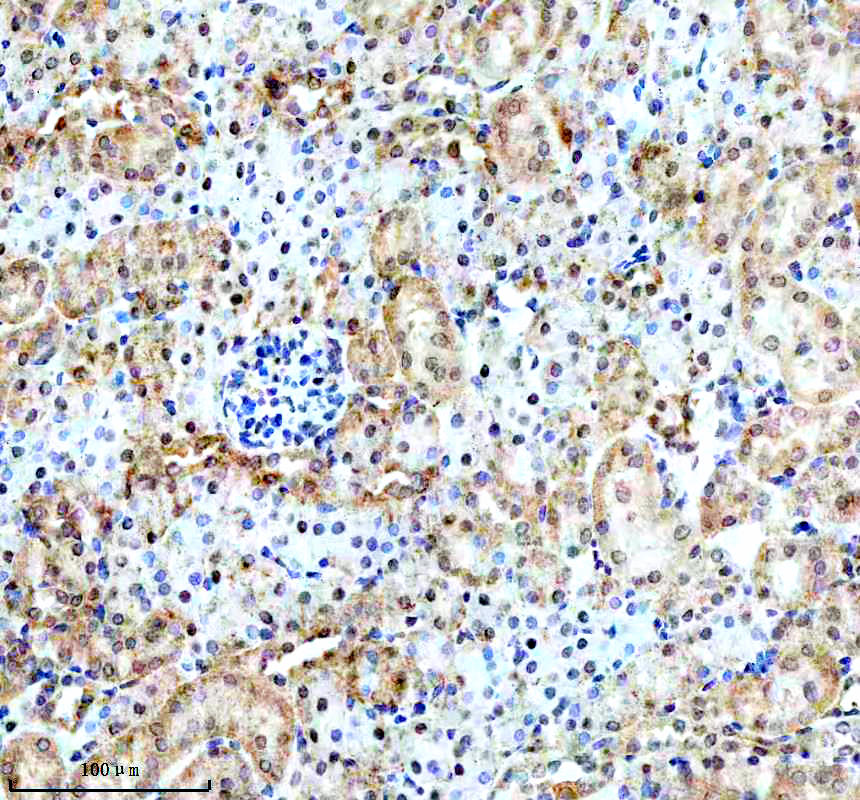

IHC analysis of BNIP3L using anti-BNIP3L antibody (BM5174) .

BNIP3L was detected in a paraffin-embedded section of mouse kidney tissue. The tissue section was incubated with rabbit anti-BNIP3L Antibody (BM5174) at a dilution of 1:200 and developed using HRP Conjugated Rabbit IgG Super Vision Assay Kit (Catalog # SV0002) with DAB (Catalog # AR1027) as the chromogen.

IHC analysis of BNIP3L using anti-BNIP3L antibody (BM5174) .

BNIP3L was detected in a paraffin-embedded section of mouse kidney tissue. The tissue section was incubated with rabbit anti-BNIP3L Antibody (BM5174) at a dilution of 1:200 and developed using HRP Conjugated Rabbit IgG Super Vision Assay Kit (Catalog # SV0002) with DAB (Catalog # AR1027) as the chromogen.